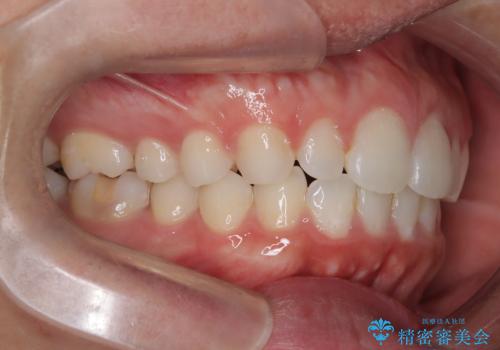

奥歯の噛み合わせもきちんと仕上げることができました。